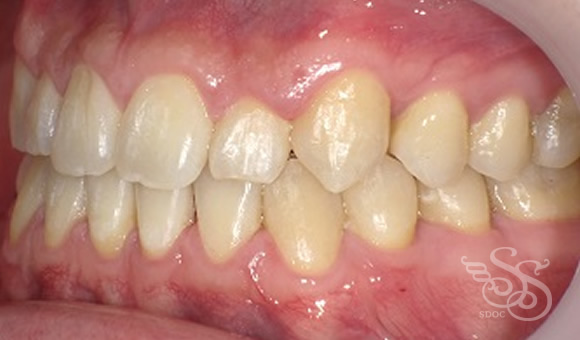

右側:術前

右側:術後